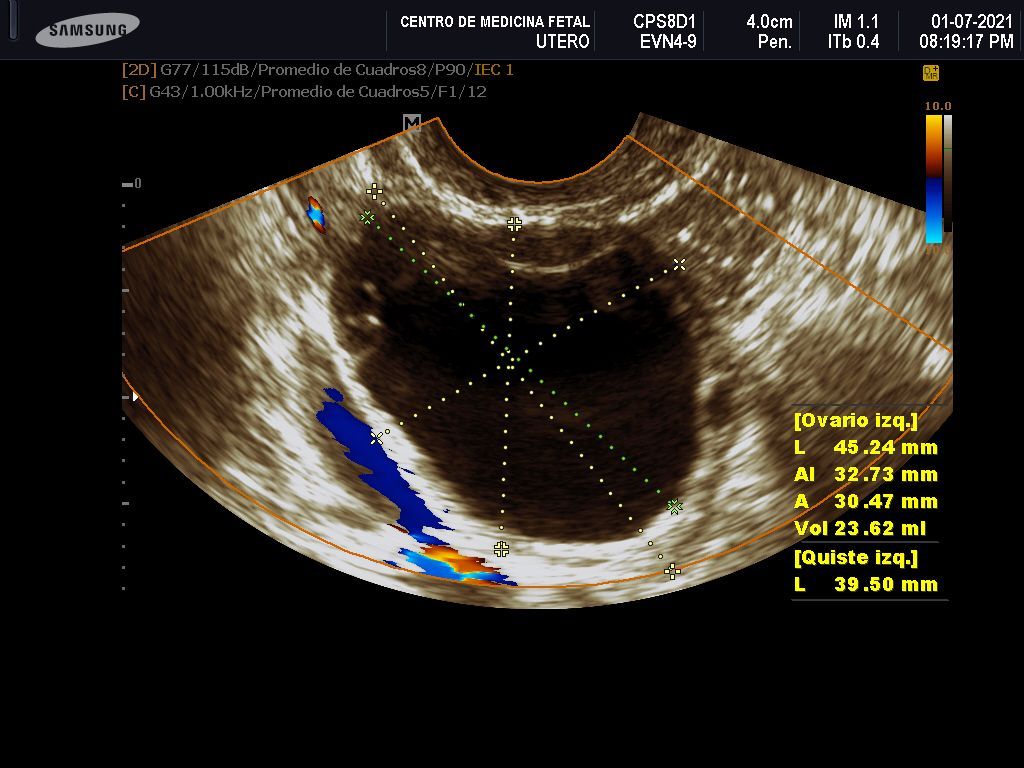

- Detección ecográfica transvaginal o pélvica y tratamiento de: Miomas, quistes de ovario, endometriosis, malformaciones uterinas